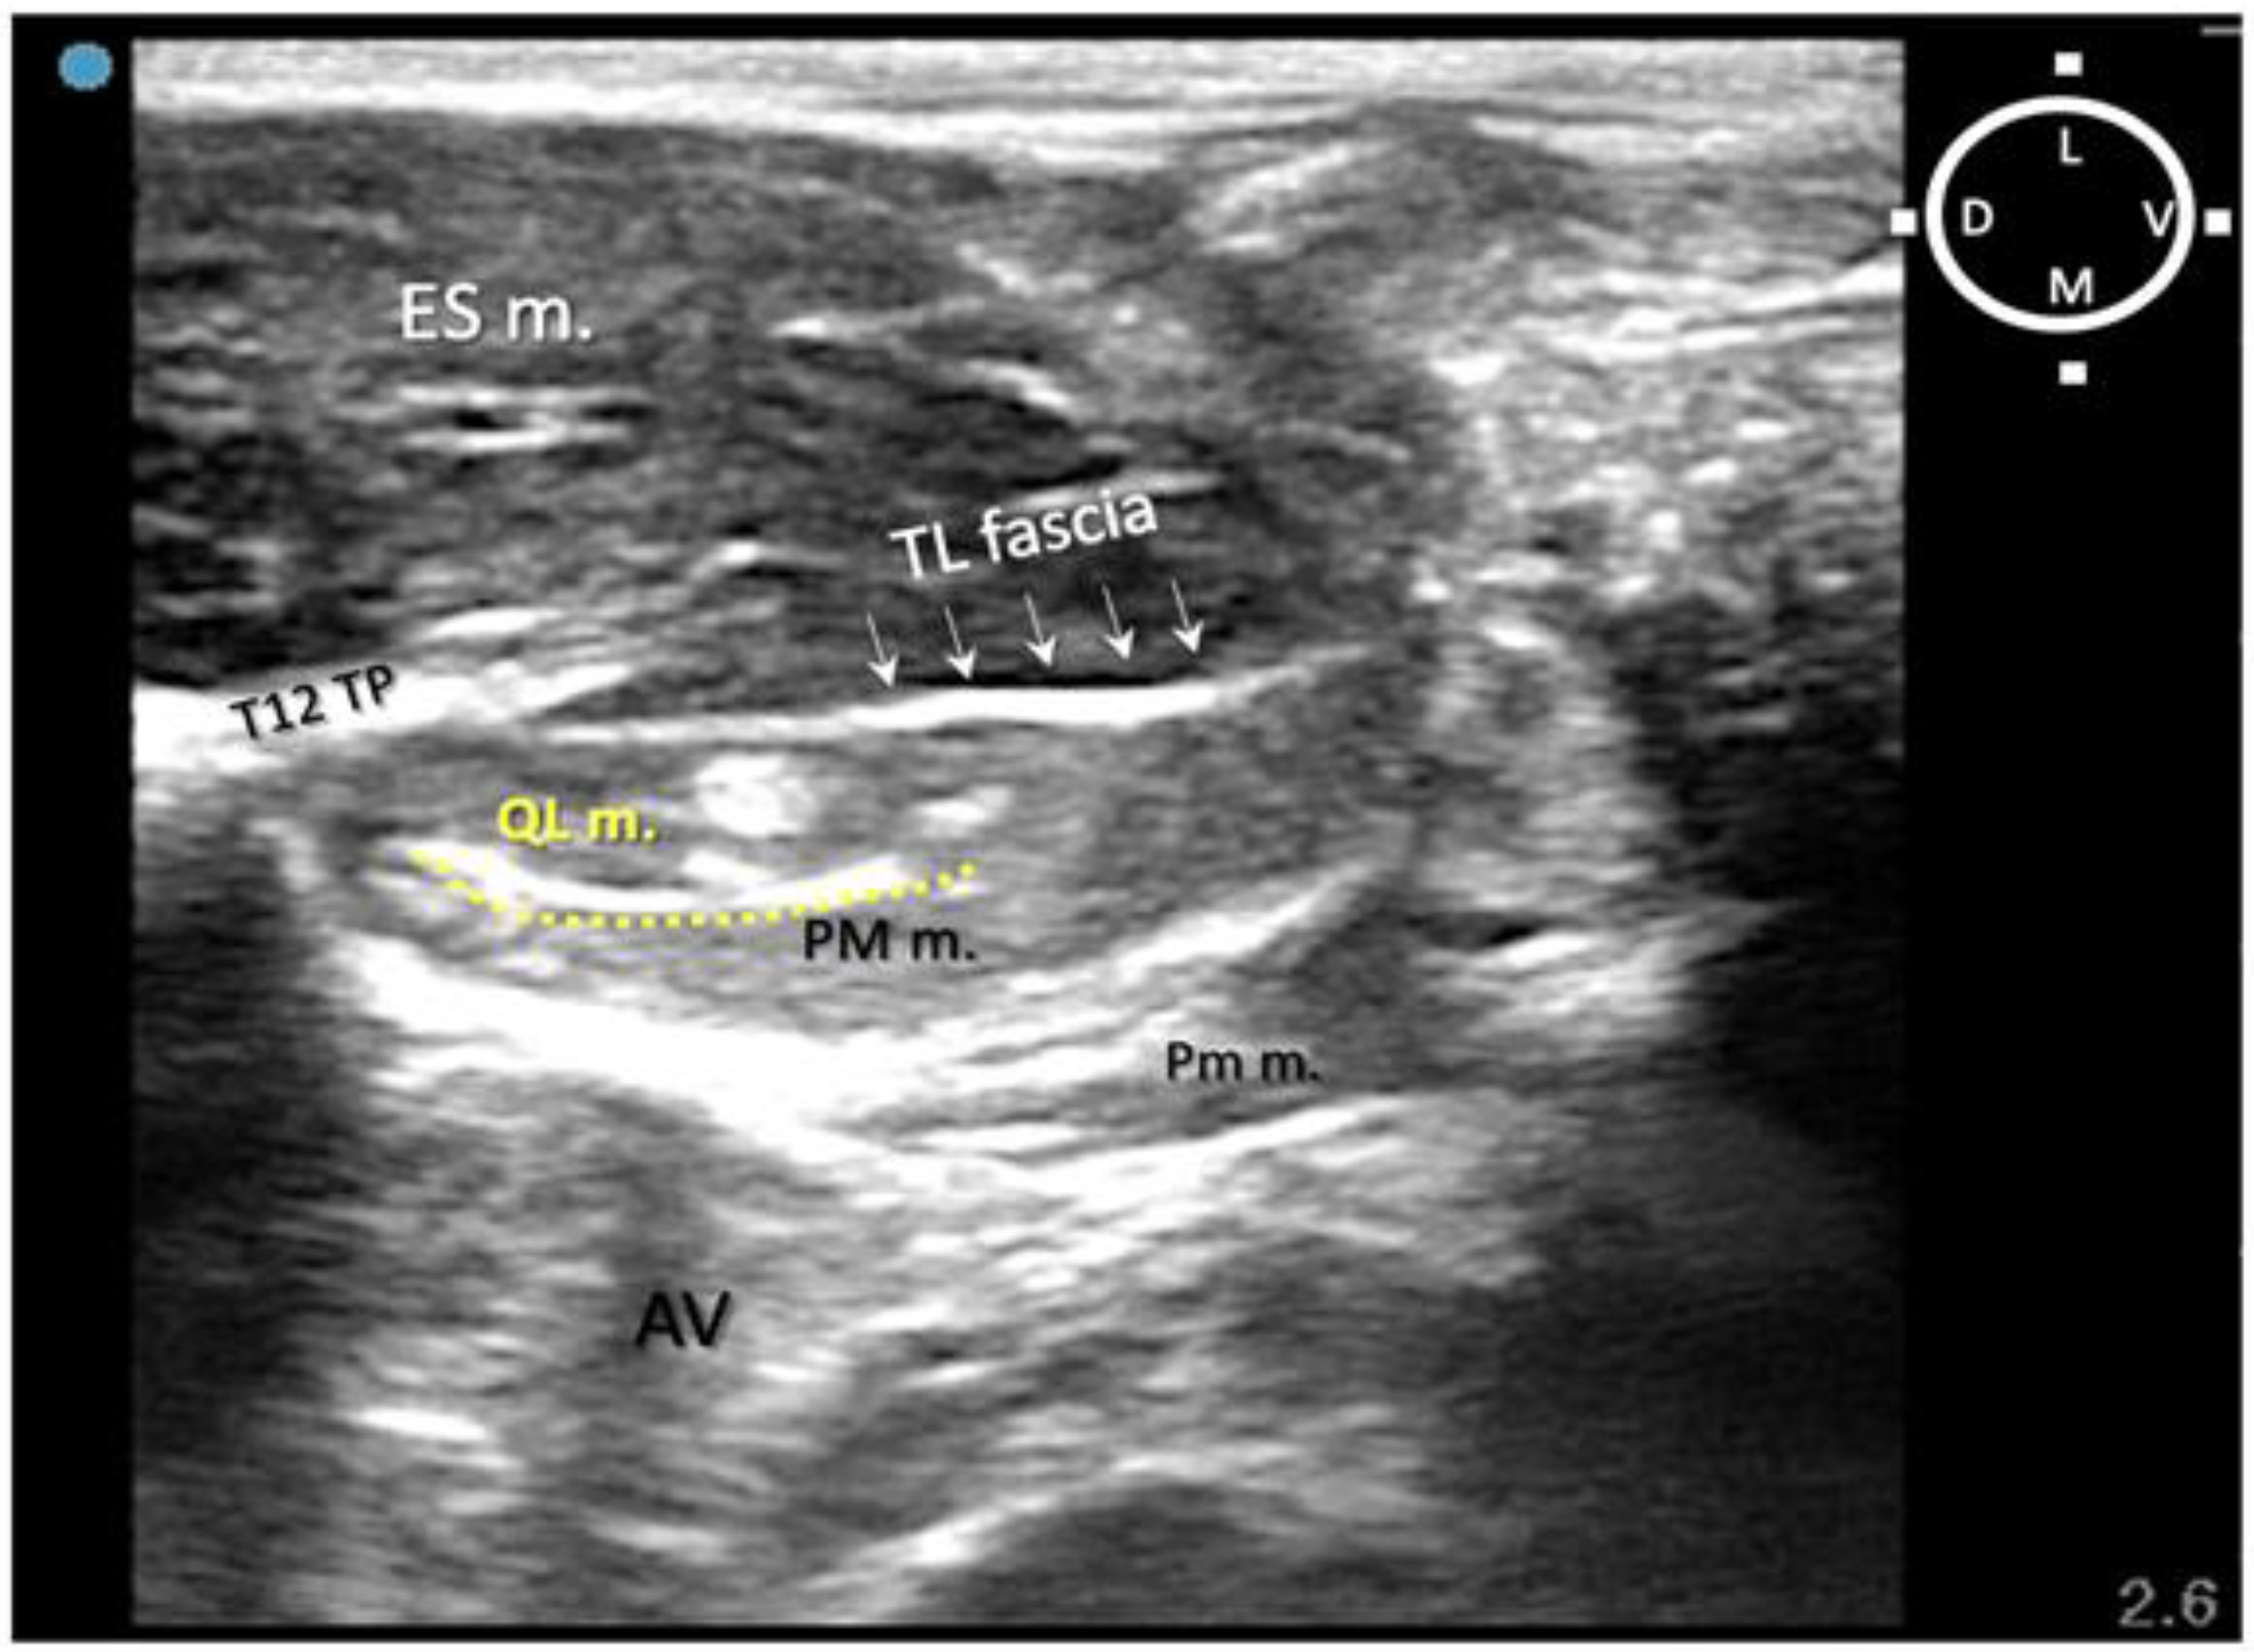

In relation to the surrounding structures, the erector spinae muscles (particularly developed in rabbits) were located dorsally to the thoraco-lumbar fascia and the quadratus lumborum muscle, which was located dorsally and medially in relation to the psoas major muscle within the same acoustic window (range of depths between 1 and 2 cm). During the insertion of the needle, the tip and shaft were always visible in 8/10 rabbits (16/20 QLBs). In order to reach the targeted fascia, the needle was passed through the erector spinae muscles, pierced the thoraco-lumbar fascia, passed through the QL muscle and finally reached the target, the quadratus lumborum fascia. This fascia surrounds the QL muscle and separates it from the PM muscle. The mean depth of the targeted area of injection (QL fascia) was recorded as 1.5 ± 0.09 cm amongst all cadavers (Figure 6A,B).

Figure 6. (A) Ultrasonographic image of the thoracolumbar area at the level of L1. The quadratus lumborum muscle (QL m.) is located ventrally to first lumbar vertebrae transverse process (L1 TP) and dorsally to the psoas major muscle PM m. The tip of the needle was introduced with a dorsomedial approach trough the thoracolumbar (TL) fascia aiming the quadratus lumborum fascia (asterisks) which separates the QL m. from the PM m. (B) Ultrasonographic image following injection of lidocaine 2%, permanent yellow tissue dye and iodine contrast (3:1:1) (black arrows) within the quadratus lumborum fascia separating PM m. from QL m. AV abdominal viscera; ES m. erector spinae muscles; D dorsal; L lateral; L Kidney left kidney; M medial; Pm m. psoas minor muscle; V ventral. Cyan blue dot represents the probe marker pointed dorsally.